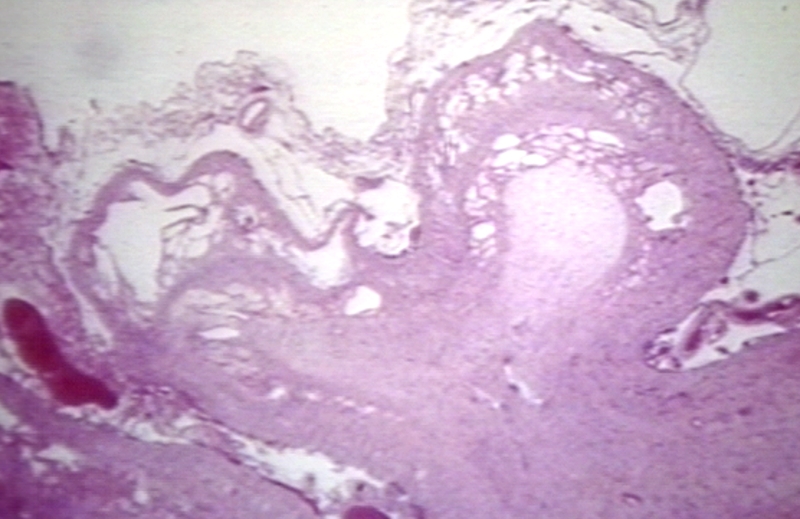

HISTOLOGY: NERVOUS: BRAIN: ENCEPHALOPATHY, HYPOXIC, CYSTIC